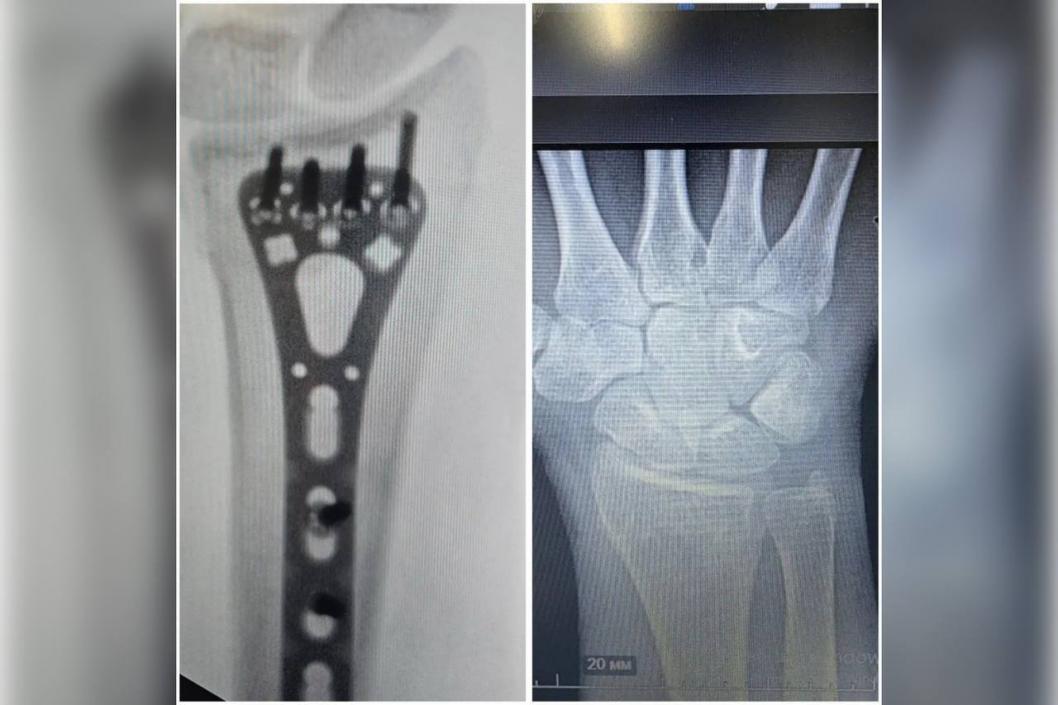

– Современные методы лечения могут помочь полностью восстановиться после серьезной травмы. Одна из наших пациенток попала в аварию на мотоцикле и получила перелом лучевой кости со смещением, – рассказал заведующий Центром реконструктивной микрохирургии кисти Иван Быркэ.

Для восстановления анатомии кости пациентки врачи зафиксировали ее фрагменты титановой пластиной и винтами. Затем они составили индивидуальный план реабилитации: она ежедневно выполняла упражнения для восстановления подвижности и силы руки под контролем реабилитологов. Через полгода девушка вернулась к привычному образу жизни.